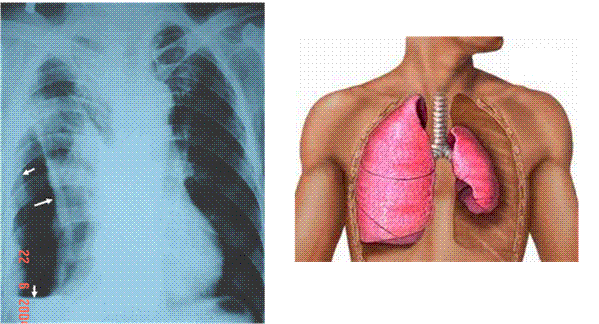

Tràn khí màng phổi

là một biến chứng nặng của lao phổi.